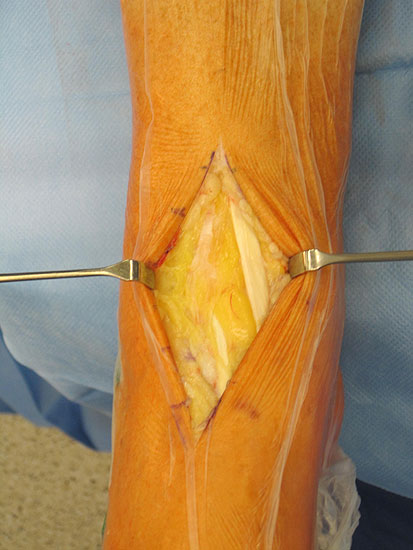

• Prothesenplanung anhand von Röntgenschablonen (Abb. 1 und 2).

• Die Fersen des Patienten sollen mit dem Tischende abschließen (Abb. 3)